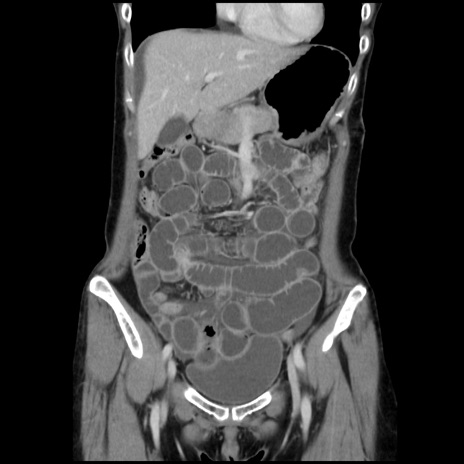

横断像

【症例】40歳代 女性

【主訴】上腹部痛、嘔気・嘔吐

【現病歴】約9時間前頃から急に上腹部痛、嘔気、嘔吐が出現。改善しないため救急要請。

【既往歴】子宮頚癌(広汎子宮全摘術、放射線療法)、腸閉塞

【身体所見】腹部:平坦、軟、腸雑音亢進、上腹部を中心に腹部全体に圧痛あり。

【データ】WBC 8400、CRP 0.03